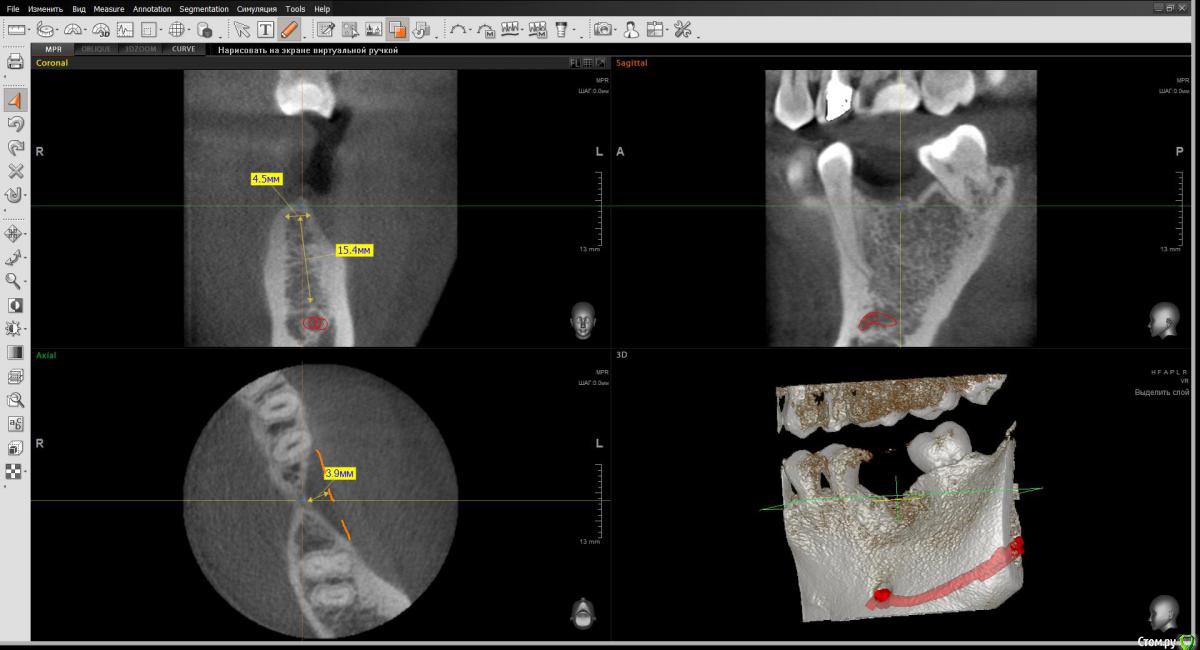

wladdX Опубликовано 1 декабря, 2016 Поделиться Опубликовано 1 декабря, 2016 (изменено) Вот пара скриншотов. Изменено 1 декабря, 2016 пользователем wladdX 1 1 Ссылка на комментарий

Powermen Опубликовано 1 декабря, 2016 Автор Поделиться Опубликовано 1 декабря, 2016 measurement_1.jpgmeasurement_2.jpgВот пара скриншотов.спасибо, что сделал скрины)) Ссылка на комментарий